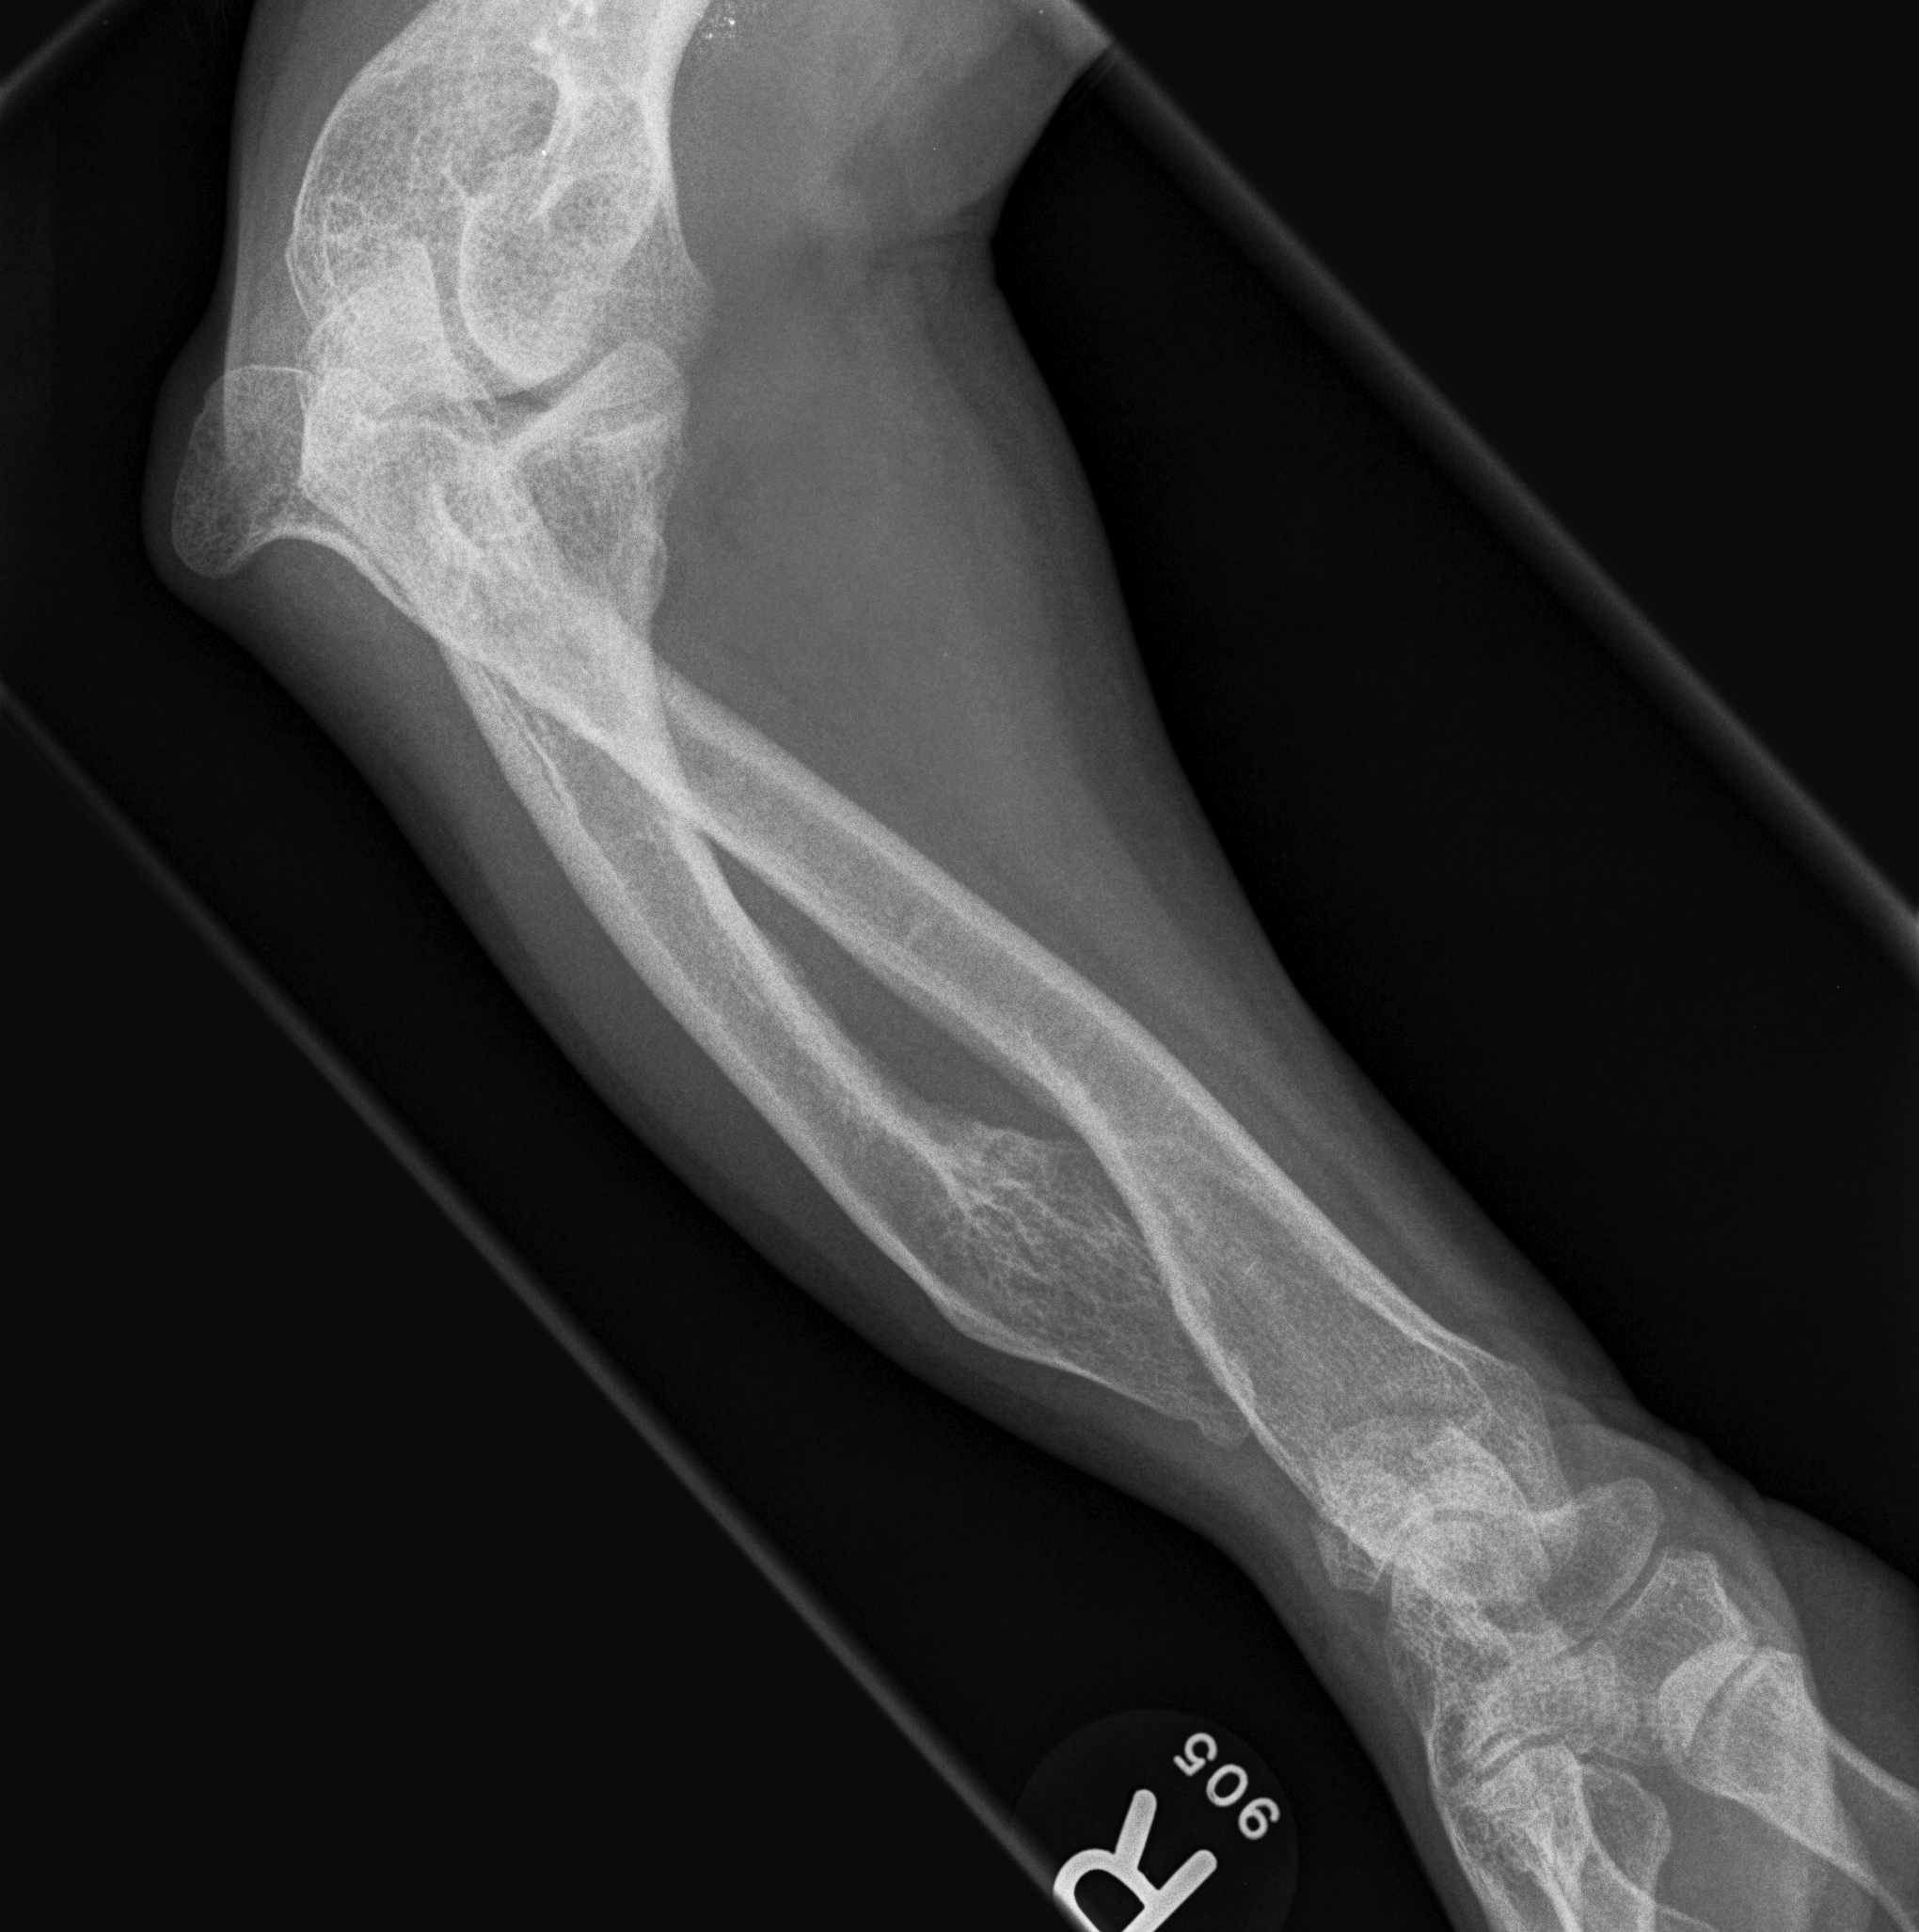

Forearm

- ulnar shortening / radial bowing / ulnar deviation of wrist

- can get radial head dislocation / carpal slip

Osteochondroma ElbowOsteochondromas Forearm 1Osteochondromas Forearm 2

Osteochondromas Forearm 1Osteochondromas Forearm 2

Incidence

Jo et al J Hand Surg Am

- 53 pediatric patients with HME

- 10% incidence of radial head dislocation